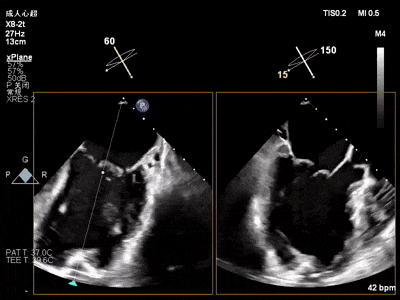

术前心超

退行性二尖瓣反流(DMR),P1/P2交界脱垂连枷(脱垂范围7mm,连枷间距4mm)

新分型:AAA型,MR 4+,VC:4×7mm

A1.5:20mm,P1.5:10mm,AP:30mm,MVA约3.8cm²

术中超声要点